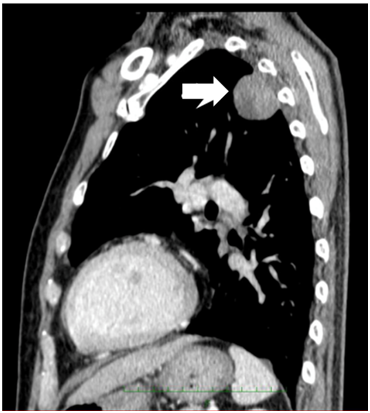

Figure 5 Chest CT. A mass shadow is present in the left upper lung field.

Figure 6 Fluorodeoxyglucose-positron emission tomography shows abnormal uptake in the left lung tumor, bilateral hilar lymph nodes, and left supraclavicular lymph nodes.